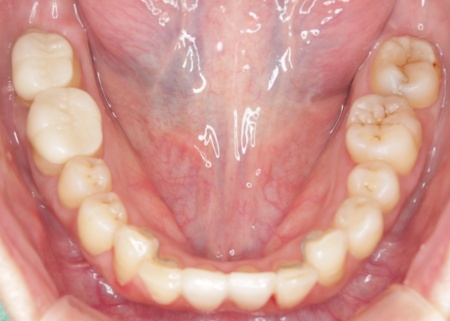

治療後

診断結果を踏まえ、まずはワイヤー矯正で歯並びと噛み合わせを整え、その後に形が変化している歯や劣化した詰め物を白いセラミック素材で作り直す治療計画を提案し、同意いただきました。 この治療方法であれば、歯を動かして噛み合わせの位置関係をしっかりと整えたうえでセラミックによる修復治療を行えます。また金属を使用しない白い素材を用いるため、見た目の違和感を抑えられます。 また、下の左右に半分埋まっている親知らず(第3大臼歯)があるため、矯正治療の際に抜歯する必要があることをお伝えし、ご了承いただきました。 まず親知らず2本を抜歯し、ワイヤー矯正治療から開始します。

矯正治療が終了したあと、セラミックによる修復治療へと移行しました。 さらにすり減って形が不揃いになっていた下中央の前歯2本には、ラミネートベニアと呼ばれる歯の表面に薄いセラミックの板を貼り付ける方法を用いて形を調整しました。 以上の工程を順に進め、すべての治療を終了しました。 |